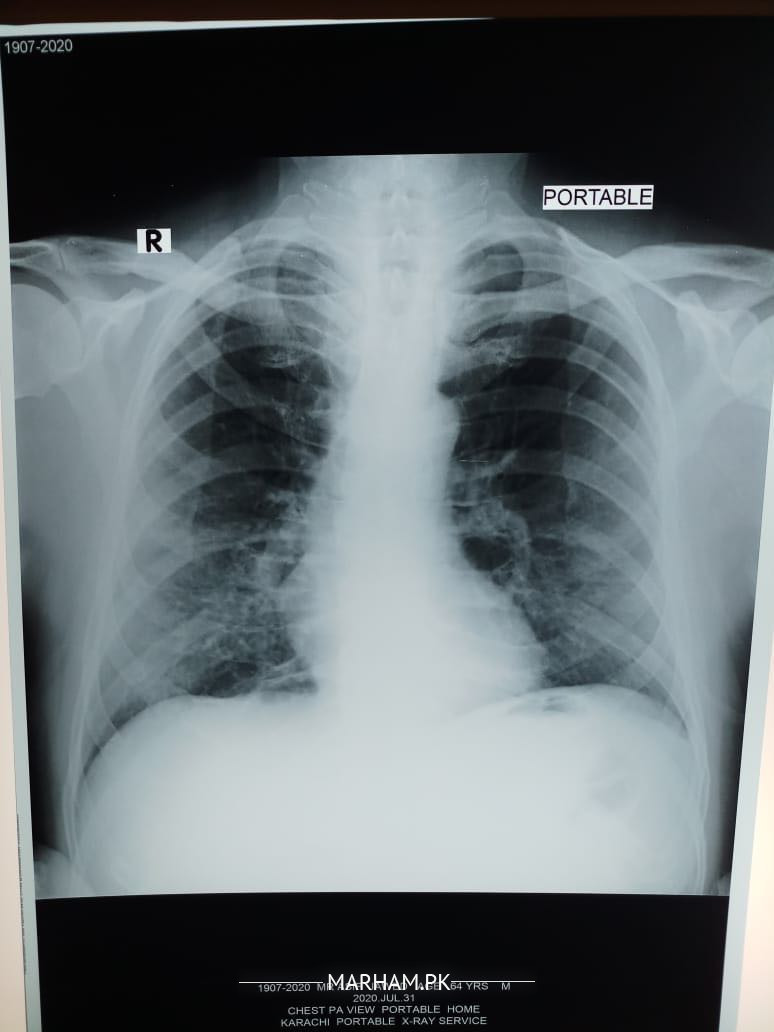

My father tested positive for corona yesterday. He has had fever 100 101, severe weakness and cough, loss of appetite etc. We got a chest extant done today and the radiologist’s report says this “â€Fibro nodulations both mid and lower zones. Rest of the lungs are clear . Cardiac size within normal limits . No evident of pleural effusion. Costophrenic angles are clear . Bony cage is intact . Conclusion. Bilateral pulmonary infection “â€. Pls advice what can be done should he be taken to the hospital?

dear the findings in x ray can be due to corona virus infection

but they can also be due to other causes

Shortness of breath no I don’t know for sure although when he speaks he starts panting and coughing after a few sentences. He’s diabetic and hypertensive both with arthritis. This is today’s xray

Can anyone pls explain what the X-ray shows? He started antibiotic on Saturday. Azomax 500 once daily with Panadol x 2 thrice a day